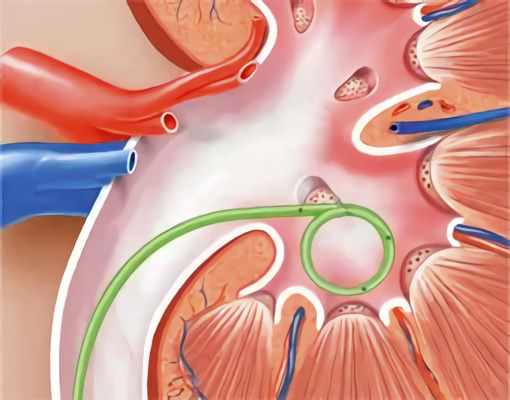

Чому виникає біль?

Стент — це тонка трубка, яку вставляють у сечовід, щоб забезпечити відтік сечі з нирки до сечового міхура. Звучить просто. Але організм може реагувати досить сильно. Контактує з інородним тілом, починає налаштовуватися, пристосовуватися, і от вам — відчуття дискомфорту або навіть біль.